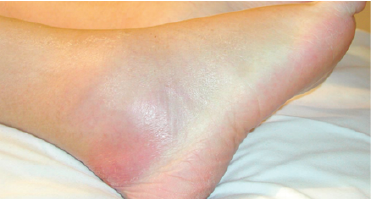

The patient hospitalized in pediatric intensive care for the severe sespis. A transthoracic echocardiography performed systematically in our patient and diagnosed a mobile vegetation of 5 mm on the atrial side of the mitral valve (Figure 3), related to mitral endocarditis, with minimal pericardial effusion.

Figure 3: Apical Echocardiogram Section Showing Mitral Vegetation